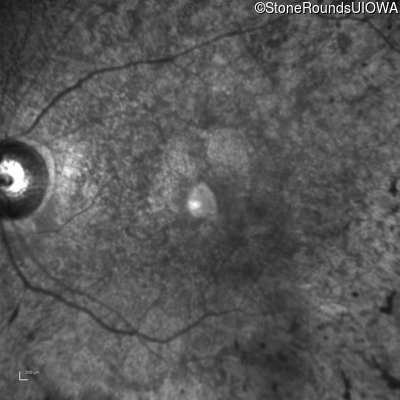

AR Retinitis Pigmentosa (IA1aiii)

Age at visit: 43 years

This 43 year old woman has had poor peripheral vision and poor night vision since childhood. She recalls sometimes having to back-up to find something she dropped on the floor. She first came to ophthalmologic attention at age 10 when there was concern for cataract formation associated with high doses of oral steroids she was receiving for asthma.